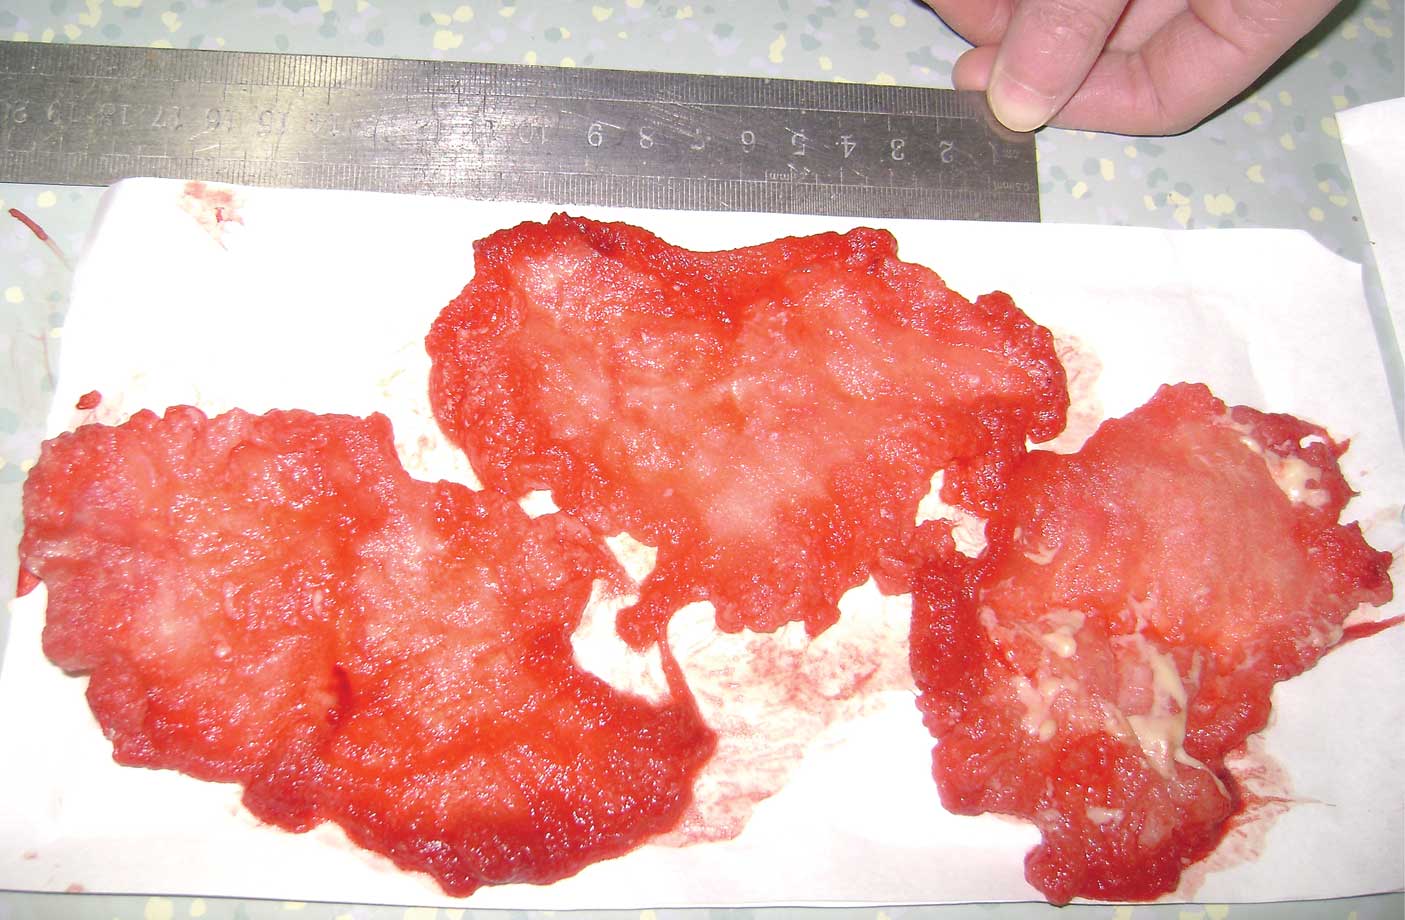

local recurrent GIST. During the exploration, a mass wrapped in a

fibrous capsule that adhered to the gastric fundus and spleen was

identified, with the same diameter as measured by CT. Following en

bloc removal, the mass was dissected and identified as a quantity

of retained local hemostat residue and pus (Fig. 4). Microscopic examination revealed a